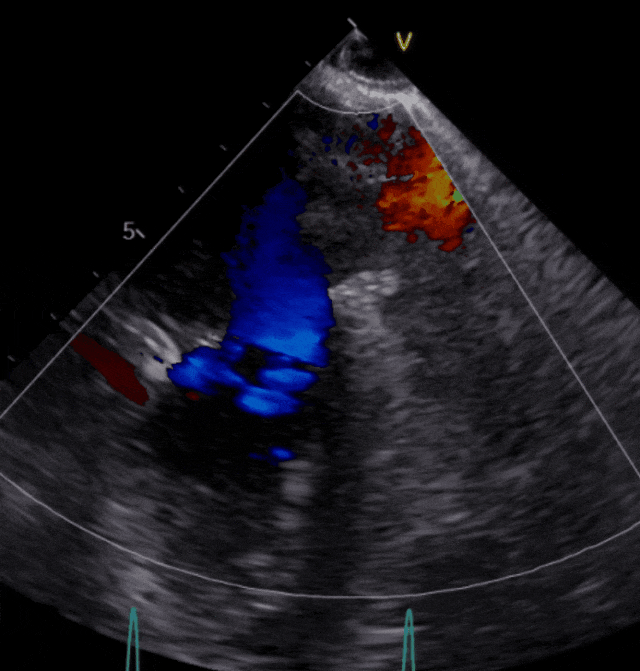

▲患者术后超声影像

手术经股静脉置管,房间隔穿刺并置入导引导管后,送入第一枚NTR,经过左房定位到达反流位置,准确捕获并夹合前、后瓣反流严重部位,原本重度的二尖瓣反流降低为中度,决定植入第二枚NTR,最终反流降低至轻度,超声评估夹子夹合稳定、肺静脉逆流改善、平均跨瓣压差3.17mmHg,患者各项生理指标正常,手术顺利完成。